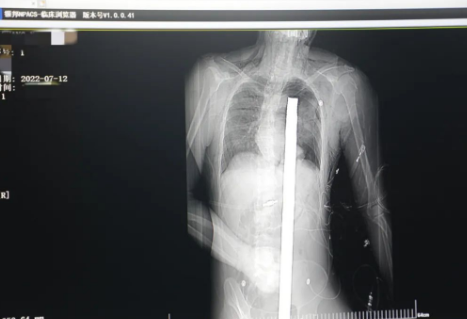

突發(fā)!太疼了,1.2米長(zhǎng)的螺紋鋼從男子會(huì)陰部垂直穿入胸腔......7月12日下午16時(shí)10分,西安一處工地的一名26歲工友,不慎從10多米的高空墜落,不幸的是工地上一根直徑3厘米的螺紋鋼從男子會(huì)陰部垂直穿入體內(nèi),工地上的工友們小心翼翼地將連著的鋼筋截?cái)?。情況危急,立即送往西安國(guó)際醫(yī)學(xué)中心醫(yī)院急救中心,此時(shí)正是下午17時(shí)00分。

時(shí)間就是生命!此時(shí),西安國(guó)際醫(yī)學(xué)中心醫(yī)院展開(kāi)了一場(chǎng)與生命賽跑的搶救,第一時(shí)間開(kāi)辟綠色通道,急診X光片及CT顯示:異物經(jīng)會(huì)陰部貫穿盆腔、腹腔到達(dá)左側(cè)胸腔主動(dòng)脈弓水平。醫(yī)院創(chuàng)傷中心立即啟動(dòng)應(yīng)急預(yù)案,劉延彤副院長(zhǎng)親臨指揮,下午17點(diǎn)48分,當(dāng)患者被送達(dá)手術(shù)室,胸外、心外、肝膽外科、胃腸外科,泌尿外科及麻醉科等多學(xué)科專(zhuān)家聯(lián)手對(duì)這名工友進(jìn)行“縱劈胸骨 前外側(cè)開(kāi)胸探查 氣管及主支氣管修補(bǔ) 肺修補(bǔ) 血胸清除 開(kāi)腹探查止血 腹膜后及盆腔探查......”手術(shù)。

情況緊急!術(shù)中探查后發(fā)現(xiàn),長(zhǎng)120cm直徑3cm的螺紋鋼經(jīng)患者右側(cè)會(huì)陰部穿入,傷及直腸,途徑膀胱后方,左側(cè)髂總動(dòng)靜脈之間傷及左腎后,經(jīng)胰腺后方在肝脾之間穿破膈肌,在下肺靜脈前方穿入左肺穿破氣管及左右主支氣管膜部,止于主動(dòng)脈弓下水平,穿入體內(nèi)的部分達(dá)到75cm。